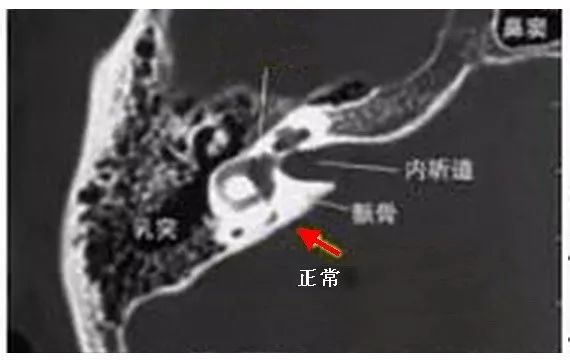

门诊接诊医生以“突发性耳聋”收入院治疗然而医生通过颞骨薄层CT检查发现可不是那么回事有大问题啊!

该患者双侧颞骨岩部后缘中部出现了明显的“喇叭口”样骨质缺损,是非常典型的“大前庭导水管综合症(LVAS)”。